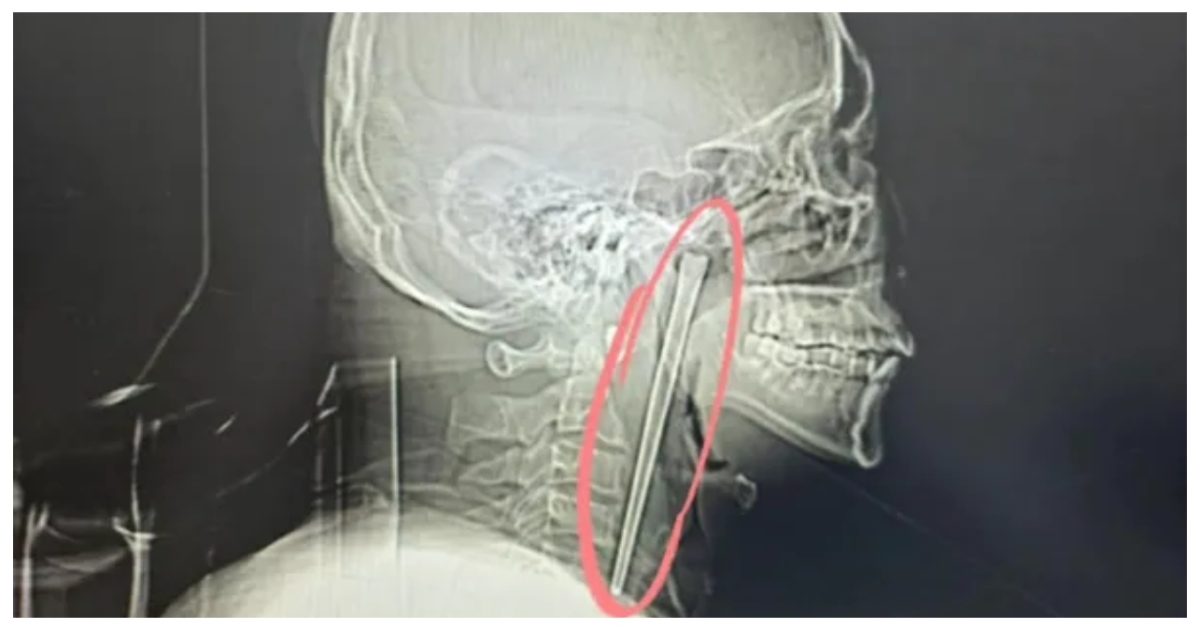

முதலில் சளி அல்லது தொற்று பாதிப்பு என கருதிய மருத்துவர்கள், வலி நீடித்ததால் எக்ஸ்ரே எடுக்க முடிவு செய்தனர். அந்தப் படத்தை பார்த்தவுடன், மருத்துவர்களும் நோயாளியும் அதிர்ச்சியில் உறைந்தனர். தொண்டைப் பகுதியில் கூர்மையான உலோகப் பொருள் சிக்கியிருப்பது தெளிவாக தெரிந்தது. அவர் தூக்கத்தில் தெரியாமலோ அல்லது தவறுதலாக விழுங்கியிருக்கலாம் என சந்தேகிக்கப்படுகிறது.

இதையடுத்து மருத்துவர்கள் உடனடியாக அறுவை சிகிச்சைக்கு ஏற்பாடு செய்தனர். சிக்கியிருந்த பொருள் பாதுகாப்பாக அகற்றப்பட்டது. சரியான நேரத்தில் மருத்துவமனைக்கு சென்றதே பெரிய ஆபத்தைத் தவிர்த்ததாக மருத்துவர்கள் தெரிவித்தனர்.